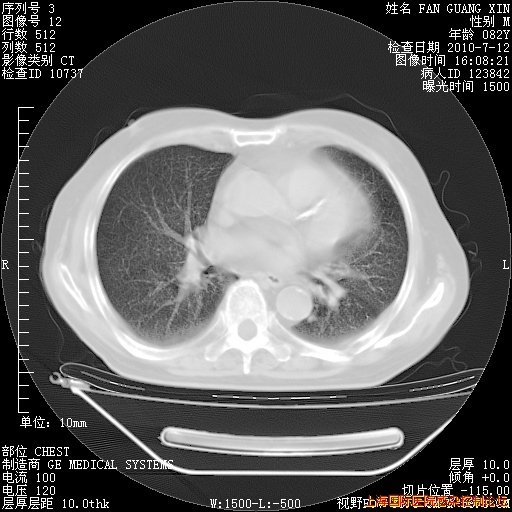

今天复查CT

今天CT

整整相隔30天的肺部CT好像有所好转啊。甲强龙减量第3天,需要观察体温。

海管,自昨日你和我通完话后,不知您岳父消化道症状有无缓解?体温怎样?阅读7.12日胸部ct,个人认为目前激素治疗是有效的,甲强龙减量是适宜的。因在抗痨治疗,需密切观察肝功、肾功能和血常规。不过,老年、长期住院和大量使用激素,很担心菌群失调发生